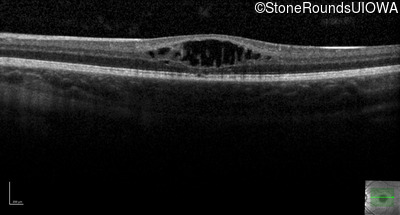

Age at visit: 7 years

OD OS

Age at visit: 9 years

Age at visit: 11 years